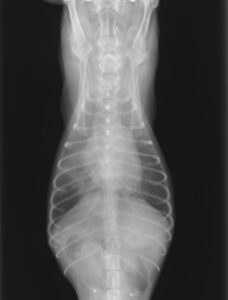

レントゲン検査

レントゲン検査では

- 心臓の大きさ

- 肺の状態

- 血管・気管・気管支の状態

の評価を行います。

後述するACVIMのステージ分類の際にもレントゲン検査による心臓のサイズの確認は重要となります。

肺水腫あり

レントゲン検査は数分で実施可能です。最低2方向以上撮影を行い評価します。

呼吸の状態が悪い子などは酸素をかがせながら行ったり、うつ伏せのみの撮影にしたりする場合もあります。